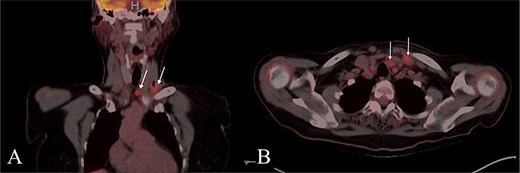

A 67-year-old woman with no significant medical history presented to her primary care provider with a growing mass at the left base of the neck. Physical exam revealed an enlarged left supraclavicular node. PET-CT showed paratracheal lymphadenopathy but was otherwise unremarkable (Fig. 1). Chest and abdominal imaging were negative, and thyroid stimulating hormone (TSH) was normal. She was referred to otolaryngology for further evaluation.

PET CT with coronal (A) and axial (B) images showing enlarged and hypermetabolic level IV and VI lymph nodes with no primary malignancy identified.